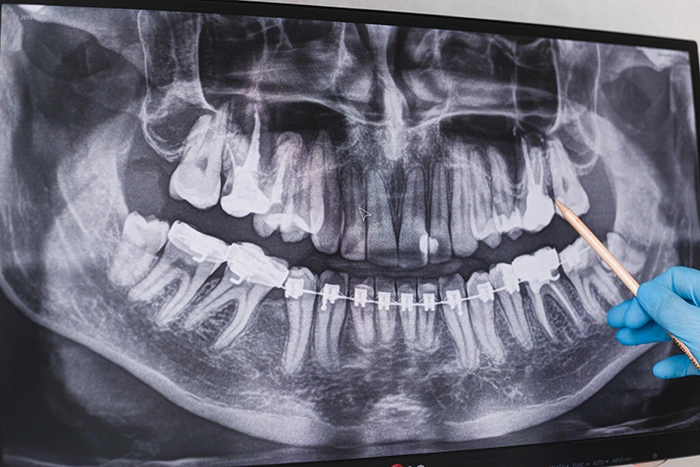

Trångt i käken I vissa fall har vi helt enkelt inte tillräckligt med plats i käken för att visdomständerna ska kunna bryta fram ordentligt. Detta kan skapa tryck på andra tänder, vilket orsakar smärta och obehag. Om visdomstanden inte kan bryta fram kan den bli delvis eller helt inbäddad i käkbenet, vilket kan leda till en rad problem.